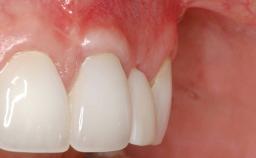

GBR and Soft-Tissue Augmentation Following Explantation to Rehabilitate a Soft- and Hard-Tissue Defect

It is sometimes necessary to remove and replace compromised implants. This case is a clear example of the need for multiple steps to achieve an optimal therapeutic result for patients with non-salvageable implants. It illustrates how the lost soft and hard tissues were rebuilt in a sequence that improved the healing of the hard tissues and assured their long-term stability. The 35-year-old healthy patient presented with clinical attachment loss on the proximal and lingual surfaces of the natural dentition. Some gingival recession was present on natural teeth, particularly in the posterior sextants (S1, S3, S4, and S6).

Soft Tissue Grafting Staged